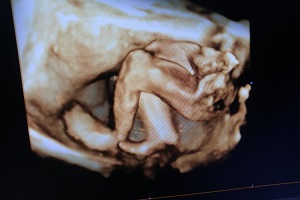

4D ANOMALY SCAN

5D SONOGRAPHY